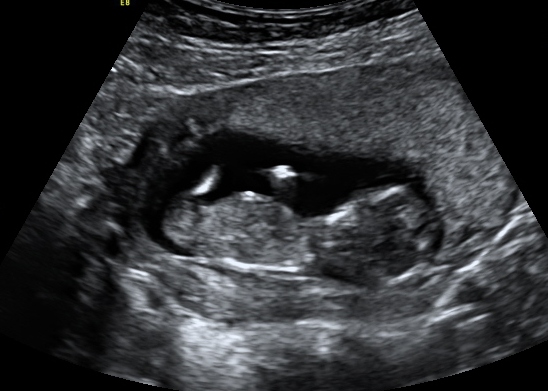

Just curious if any of you clever ladies can see any nub in either of these pics. Scan was done at 12+1 weeks.

I'm not seeing a nub.